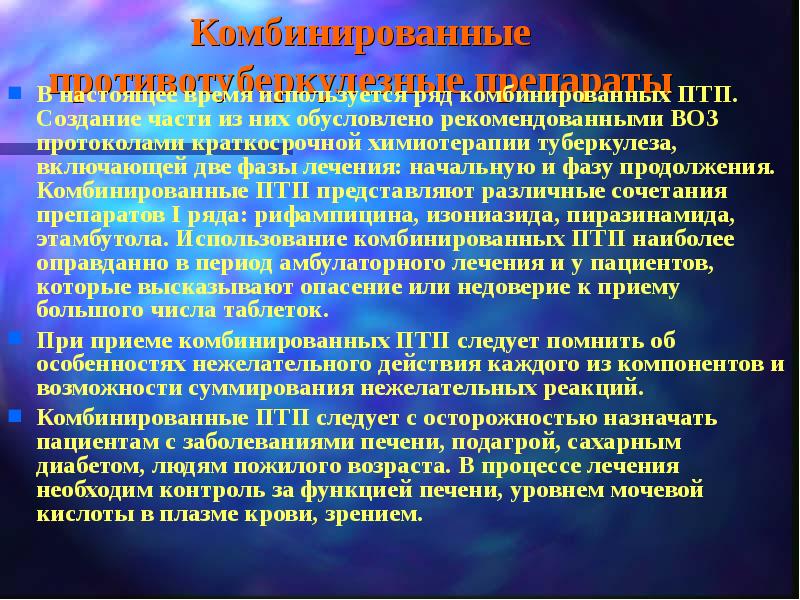

Лечение туберкулеза: Методики химиотерапии

Раздел: Визуальный дайджест